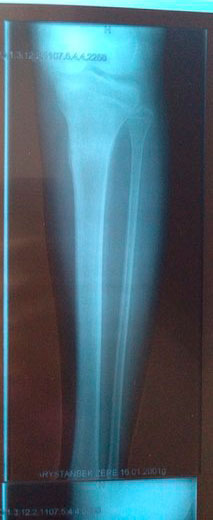

Рентген контроль в 81 день с момента снятия аппаратов.

Сращение железное, никаких ограничений! На физ-ру ходить можно! И ждём фото ножек девочки!